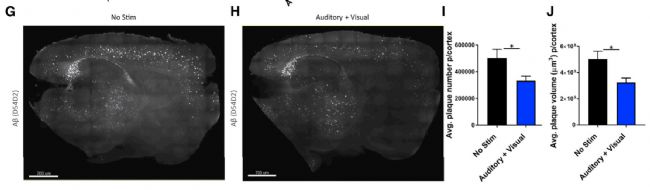

圖一:經過SHIELD透明化處理的6月齡5XFAD小鼠整腦25um矢狀面厚切片(G為無干預對照,H為視覺+聽覺GENUS干預),使用anti-Aβ plaques抗體免疫染色。

細胞外β淀粉樣蛋白沉積和細胞內tau蛋白磷酸化是AD的主要病理特征,異常的神經活動可以加劇AD的病理發展并最終破壞與高等認知功能相關的神經環路。反之,通過調控一些神經活動也被證實可以減緩AD病情。2019年,來自麻省理工學院的Martorell等人在《細胞》雜志刊登的文章中【1】,使用伽馬共振感官刺激(gamma entrainment usingsensory stimuli, 簡稱為GENUS)對5XFAD阿爾茲海默病模型小鼠進行干預。他們發現,聽覺GENUS使用音頻誘導小鼠聽覺皮層(AC)和海馬CA1區產生伽馬頻率的神經活動可以促進空間和認知記憶,并減輕相應區域的淀粉樣蛋白沉積。聽覺GENUS還引起相應區域的小膠質細胞活化和血管擴張反應,并在Tau P301S小鼠模型中減少了Tau蛋白磷酸化。而同時使用40Hz的視覺+聽覺GENUS(不能只是二者之一)更進一步地使腹內側前額葉皮層產生膠質細胞反應。為了更廣泛地探尋GENUS對于模型小鼠產生的作用,文章作者采用SHIELD方法對小鼠整腦厚切片進行了透明化處理,通過三維光片熒光顯微整腦成像和數據分析揭示出為期一周的視覺+聽覺GENUS讓小鼠整個新皮質中的淀粉樣蛋白負荷體積減少了37%,數量減少了34%(圖一)。GENUS這種無創性的干預方法在病理和行為兩方面緩解了AD模式動物的癥狀,是否能運用于人類還有待進一步證實。